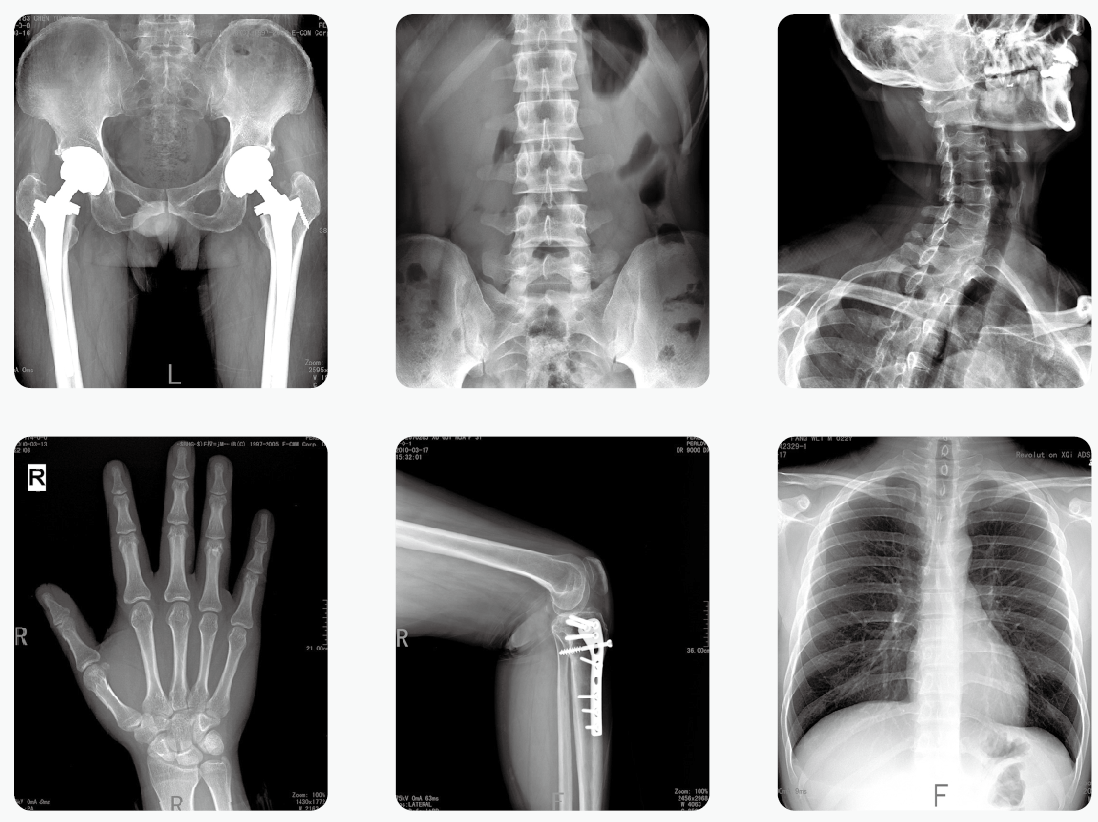

【產品臨床圖片】

移動式DR為移動式X射線攝影醫療診斷設備,可用于放射科攝影、影像科攝影、兒科攝影、體檢攝影、手術室及重癥監護室攝影,滿足對人體關節、骨骼、胸部、泌尿、婦科和特殊部位的X射線攝影要求。

PLX5200移動式dr是一款高頻組合式數字化X射線攝影醫療診斷設備,適用于放射科、骨科、病房、急診室、手術室 、ICU等處,滿足人體的頭部、四肢、胸腔、脊柱、腰椎、腹部等全身各部位的數字化攝影的工作需求。